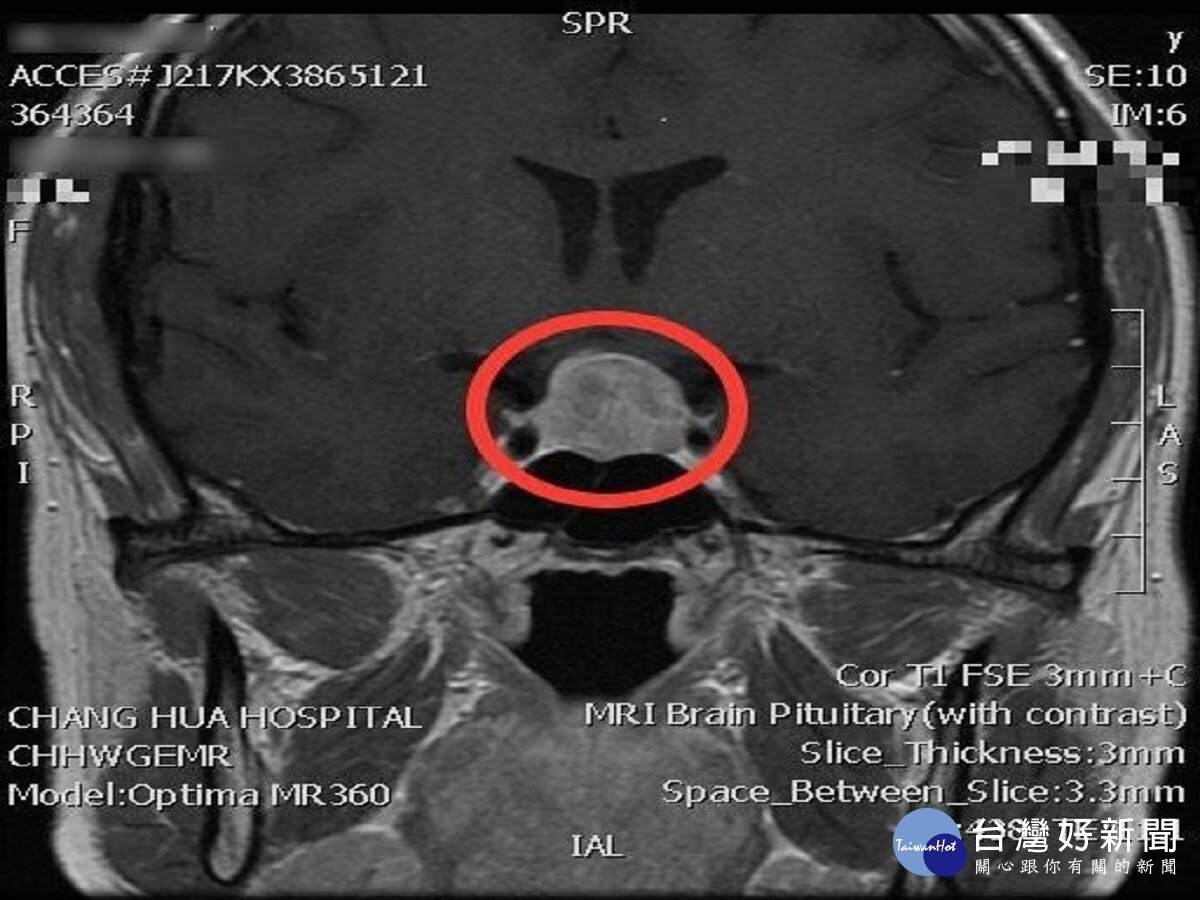

趙紹清說,經腦部核磁共振儀每年追蹤檢測患者,5年後患者的腫瘤已經大到2公分,還壓迫到視神經,進而影響視力,兩眼靠近外側的視野已經變小,開車時會看不見旁邊的人及車,走路也因視野受限而易撞到人,所以一定要手術去除腫瘤,如果不處理,不僅生活中處處是危險,當神經壓迫越來越嚴重,眼睛還有可能失明,屆時再處理可能來不及了。

趙紹清表示,手術不採取破壞範圍大的傳統開顱手術,而是經鼻腔內視鏡切除腫瘤,利用3D立體影像導航系統準確定位,內視鏡從鼻孔進入,在手術中特別以神經監測儀監測,當神經有任何損傷可能時,監測儀馬上警告,以確保患者的神經不受傷害。